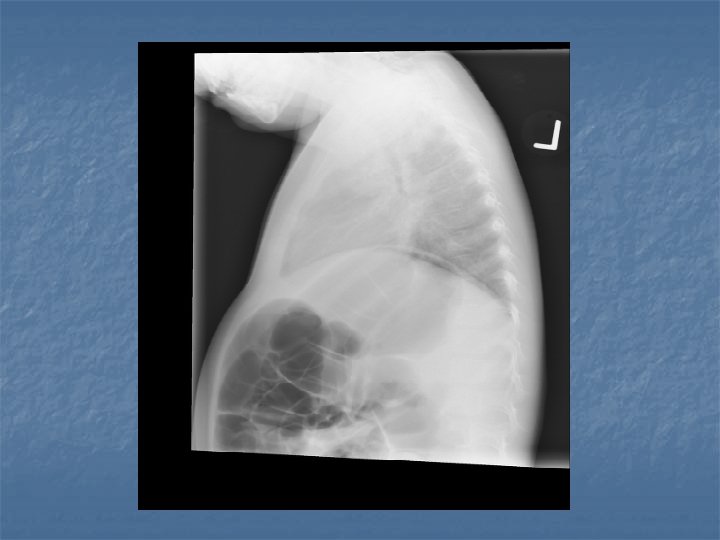

Case AJ: 11 yo male n n n N/V/D x 1 day 6 x vomitting, 2 x diarrhea Periumbilical abdo pain “Dizzy” Rhinitis, cough 38 C, HR 117, RR 28, 105/75, 96% RA

AJ’s Exam n n n Pale Small cervical nodes Abdo exam nontender No indrawing Decreased breath sounds RLL, crackles

Pediatric CAP n n Bronchopneumonia – acute inflammation smaller bronchial tubes and peribronchiolar alveoli Pneumonitis Syndrome – Infants 1 – 3 months old, afebrile with cough, tachypnea and progressive respiratory distress. n n CXR shows diffuse pulmonary infiltrates and air trapping Single or mutlipathogens involved

CXR Summary n In combination with physical exam, do a CXR when: Questionable dx n Admitting pt n <3 y with fever >39 C and WBC >15 n Complicated pneumonia suspected n

CXR Findings VIRAL n Peribronchial thickening n Diffuse interstitial infiltrates n Hyperinflation BACTERIAL n Subsegmental, segmental or lobar infiltrates n Air bronchograms n Round pneumonia in early S. pneumo n n M. pneumo diffuse infiltrates out of proportion to clinical findings (or bronchopneumonia infiltrates in lower lobes) Bilateral reticulonodular interstitial infitrates

n n n 50% bacterial pneumonia will have lobar infiltrate Can also see alveolar infiltrates Round pneumonia seen with S. pneumo